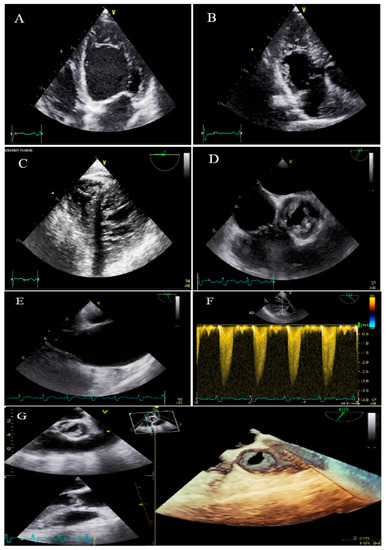

A 34-year-old lady, 34 weeks pregnant, was referred to the hospital with dyspnea, worsening over the course of the last week. A total of 2 h after admission, she experienced sudden cardiac arrest and was successfully resuscitated. At that time, the ECG monitoring was in favor of torsade de pointes. During the hospital course, intermittent complete heart block was noted. She did not report any CVD symptoms before this. Her first pregnancy was uneventful, and her healthy boy was 3 years old. TTE and TEE revealed non-compaction of the left and right ventricles, mild biventricular systolic dysfunction (global LVEF = 40%, tricuspid annular plane systolic excursion = 14 mm, and RV Sm = 8 mm), a large ostium primum ASD (34 mm), and moderate pulmonary hypertension with the pulmonary flow to systemic flow ratio (QP/QS) of 2.1 (Figure 4). During the 4-week follow-up, she developed a couple of symptomatic ventricular tachycardia, which properly resumed to a normal rhythm by electrical cardioversions. Finally, the heart team decided to schedule her for a cesarean section with temporary pacemaker backup. After the delivery of a living, healthy baby, she refused cardiac surgery. Therefore, based on the patient’s and her family’s request, she underwent implantation of a single chamber implantable cardioverter-defibrillator (ICD). During the 4-month follow-up, it did not record a high ventricular rate.

Figure 4.

Two-dimensional transthoracic echocardiographic views of case #4, (A); Biventricular apical SAX view, (B,C); Transesophageal gastric views, illustrating hypertrabeculated apical portions in addition to deep intertrabecular recesses. (D); Color Doppler echocardiography, showing evidence of direct blood flow from the ventricular cavity into deep intertrabecular recesses. (E–G); Two- and three-dimensional mid-transesophageal echocardiographic views, showing a large ostium primum type of atrial septal defect with left to right shunt. (H); Speckle tracking echocardiographic findings, compatible with myocardial performance impairment, mild in apical to severe in basal segments, and GLS = −10.9%. (I–L); Twelve-lead electrocardiography and a couple of tracings at different times, showing complete heart block and sustained runs of wide QRS tachycardia.